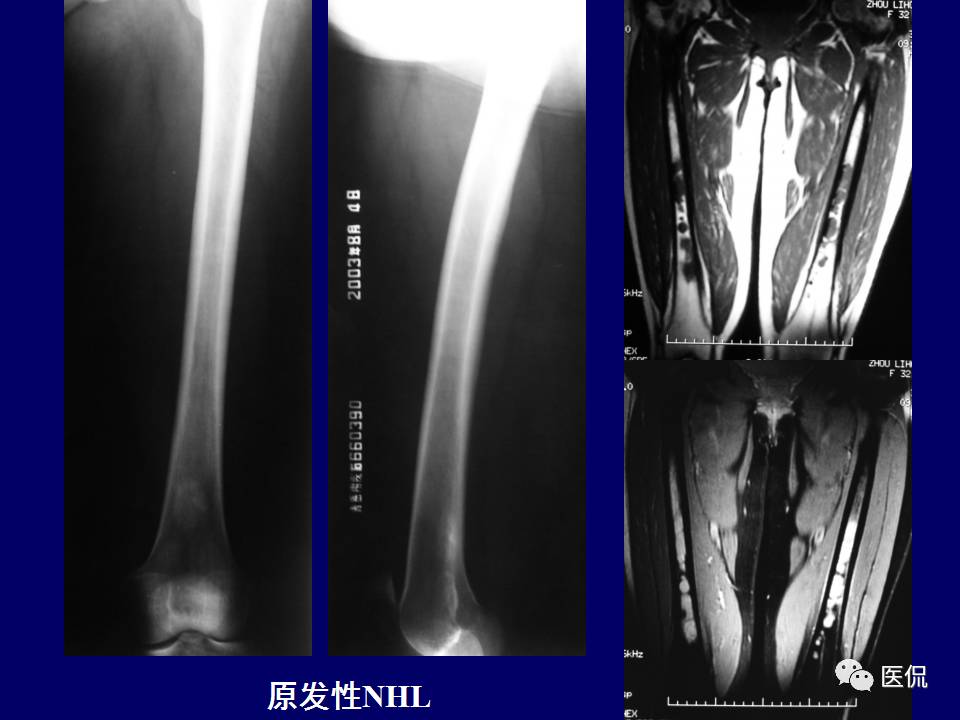

原发性骨淋巴瘤,是一种少见肿瘤。平片上干骺端单发、浸润性骨质破坏、层状骨膜反应+MR上骨髓侵犯、软组织肿块+年龄>30岁均可高度提示,影像学区分原发和继发PBL比较困难。更多知识,请往下看~